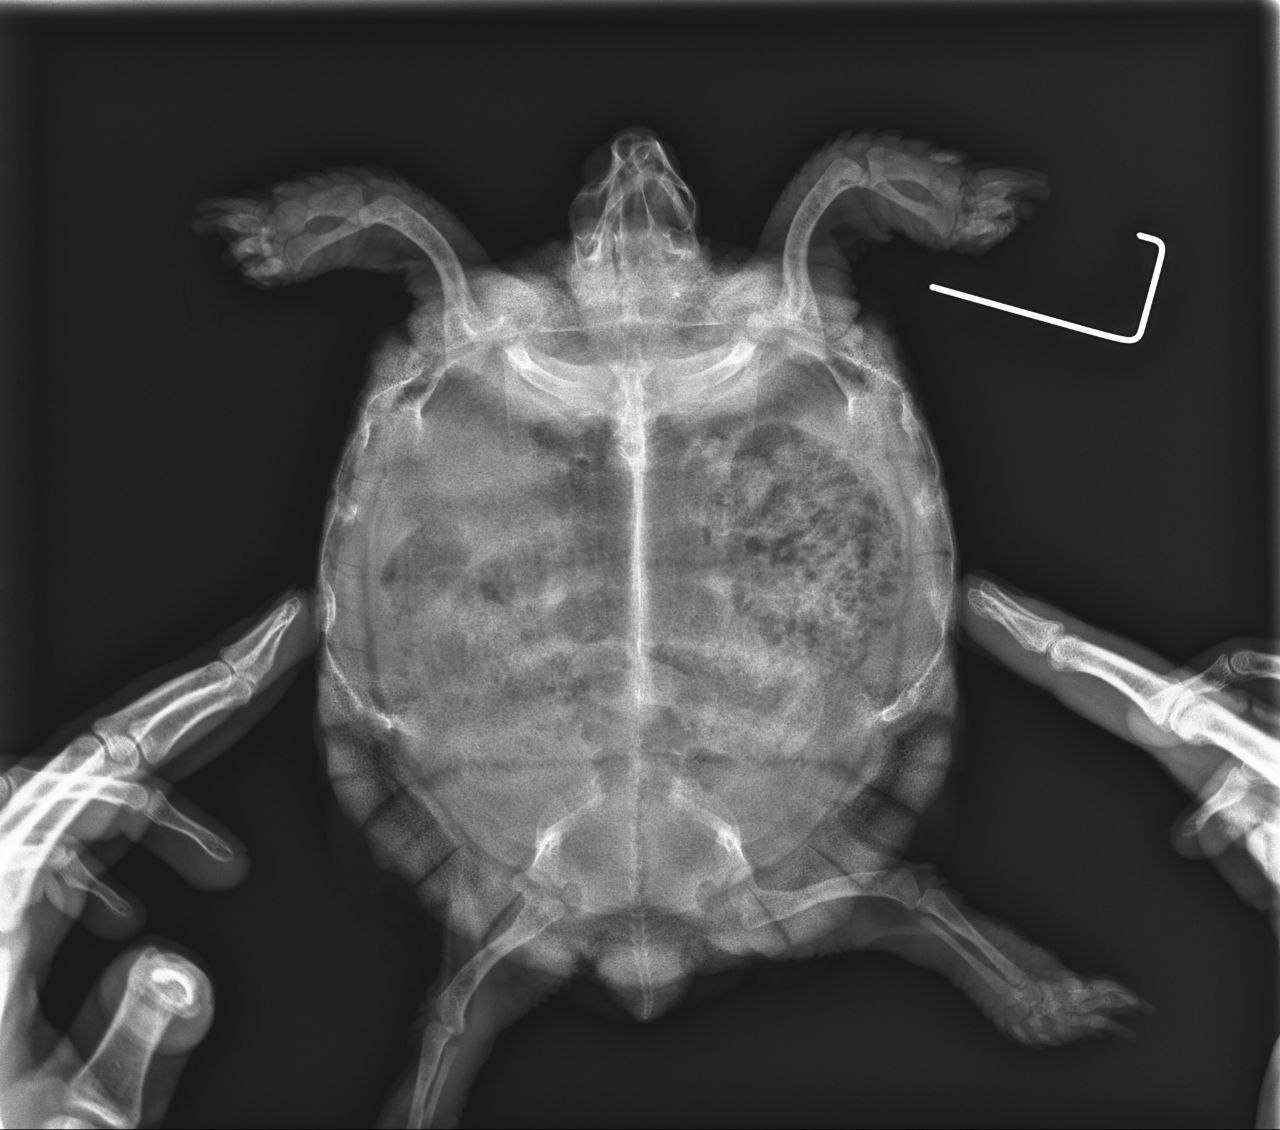

Самый актуальный рентген:

samyi-svezhii-rentgen.jpg

Во-первых в такой проекции никаких лёгких не видно, но видно, что жкт был забит газами и каловыми массами.

Для того, чтобы увидеть лёгкие нужно делать другие проекции. Поэтому лечение и диагноз были неверными. Более того, такое количество фуросемида могло добить и без того больные почки, т.к. они у всех среднеазиатов в неволе слабое место, тем более, что она раньше жила под батареей.